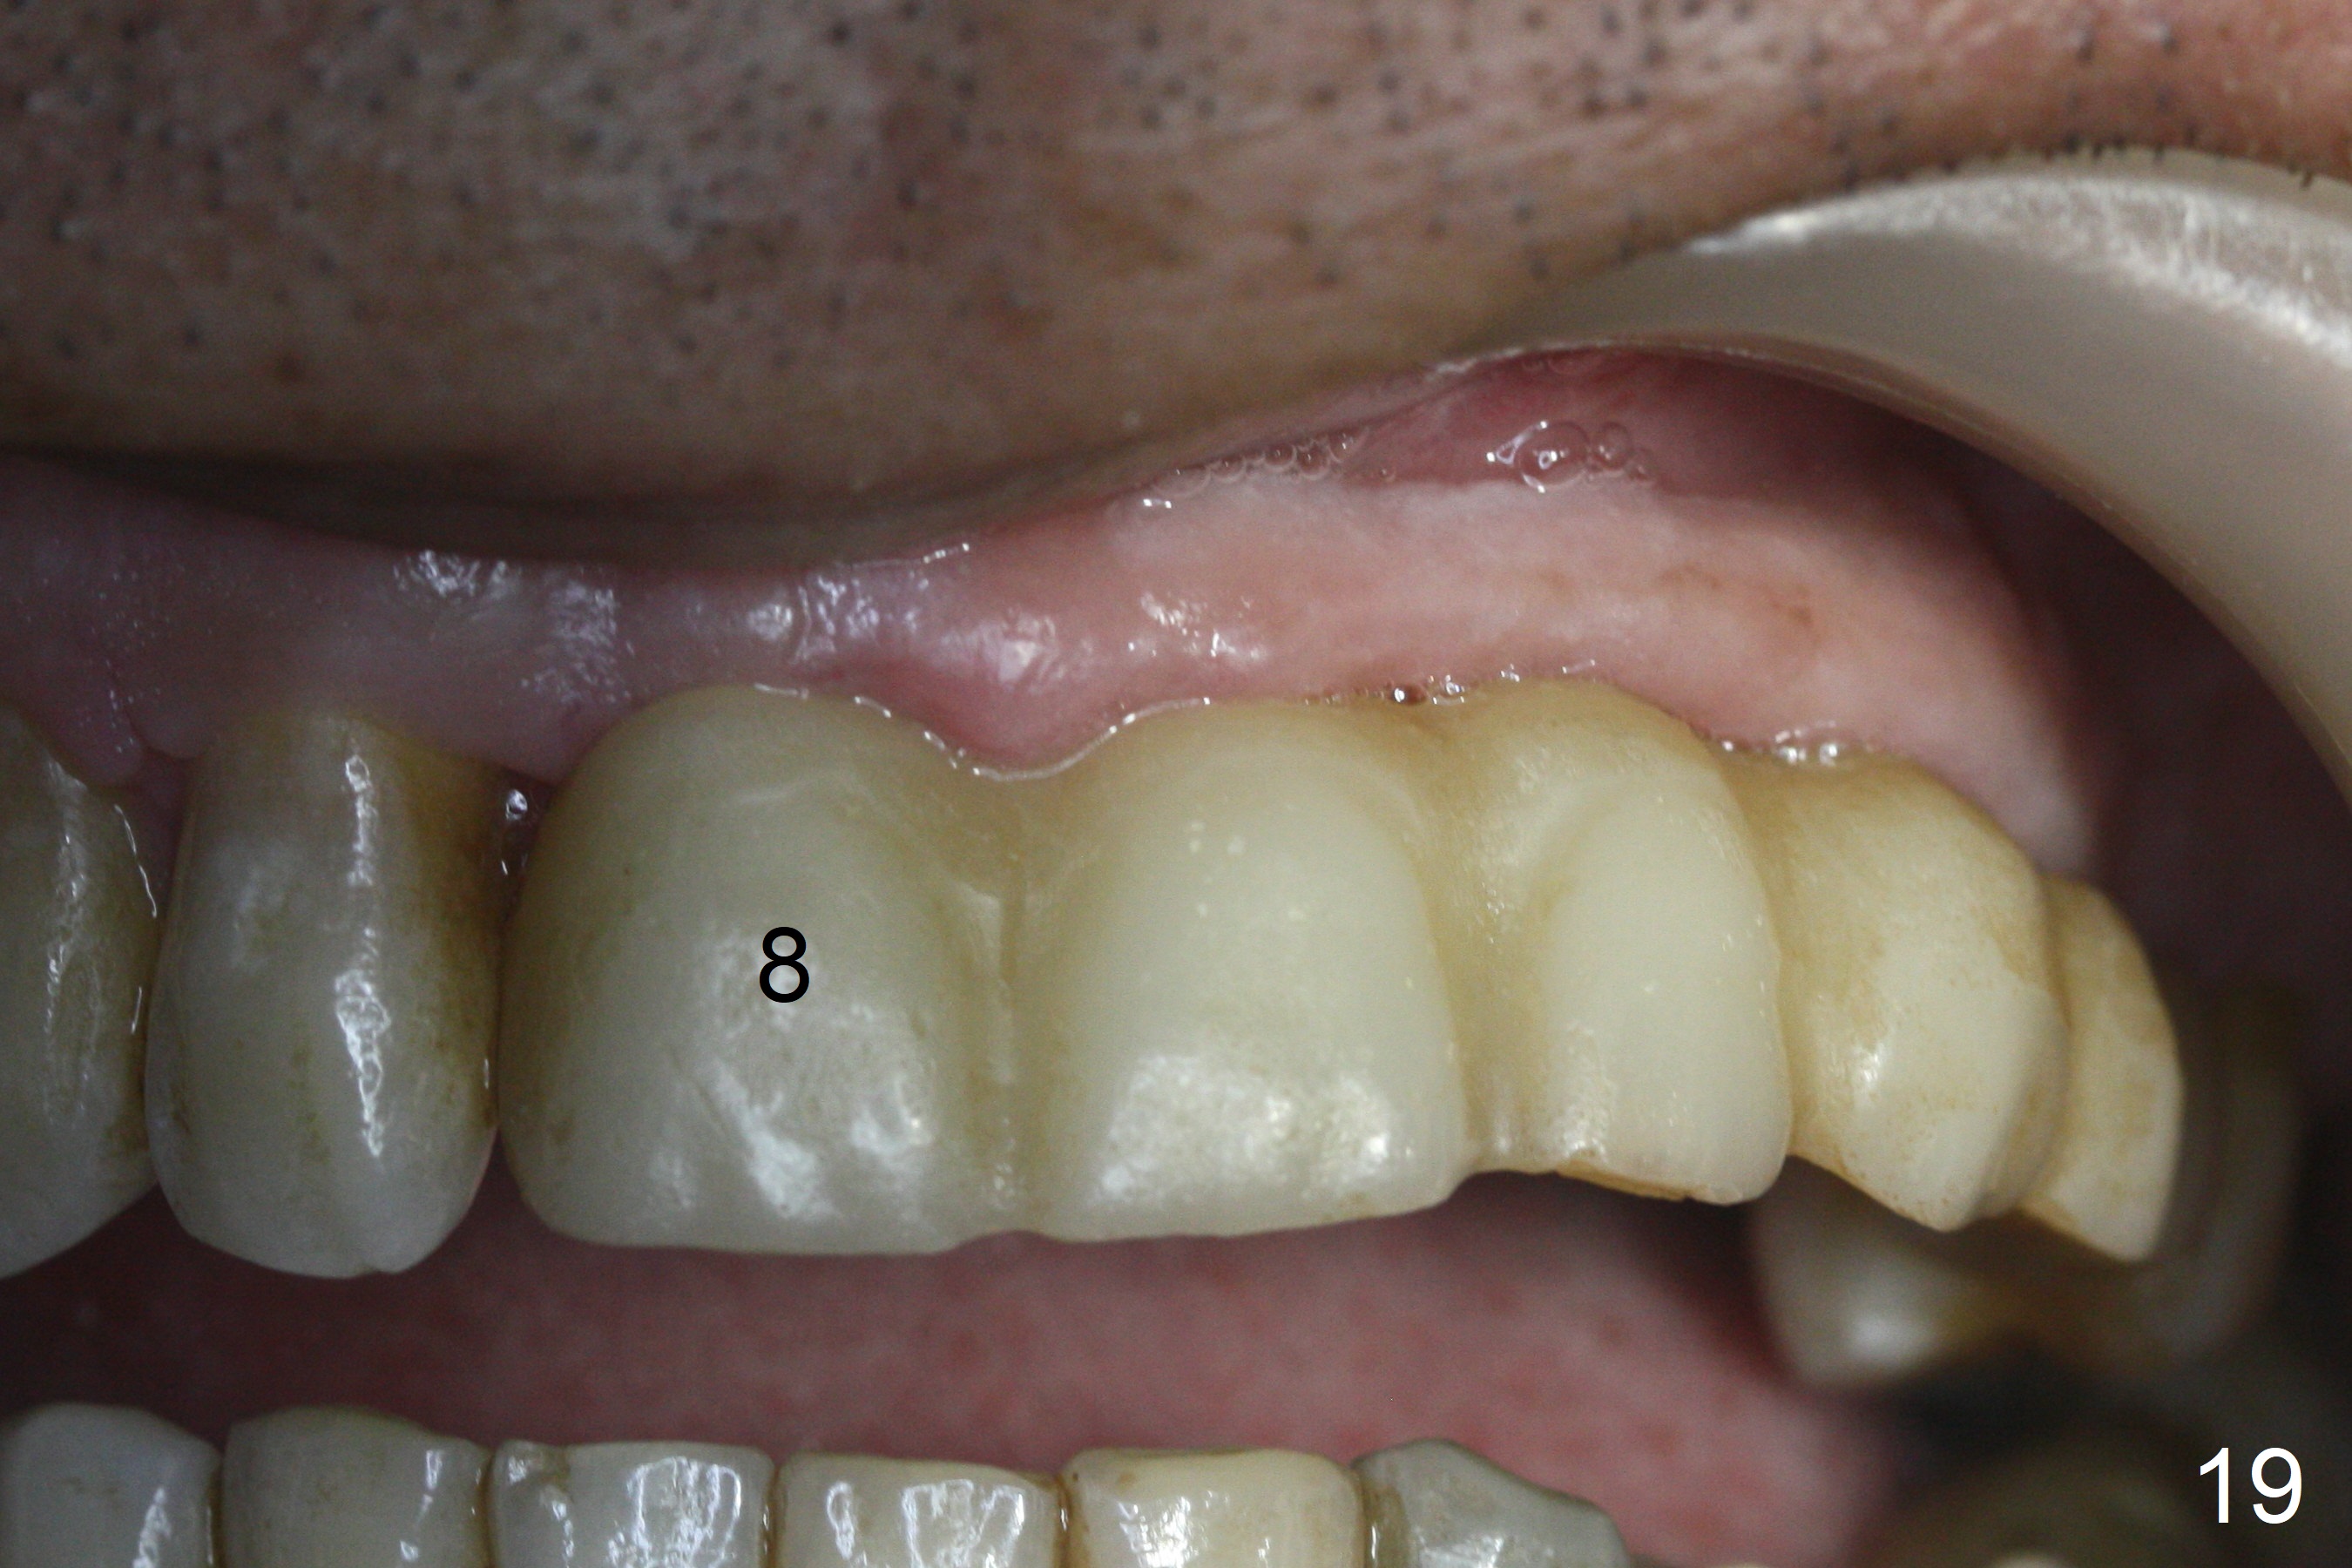

The soft tissue heals 2 weeks postop (Fig.19).